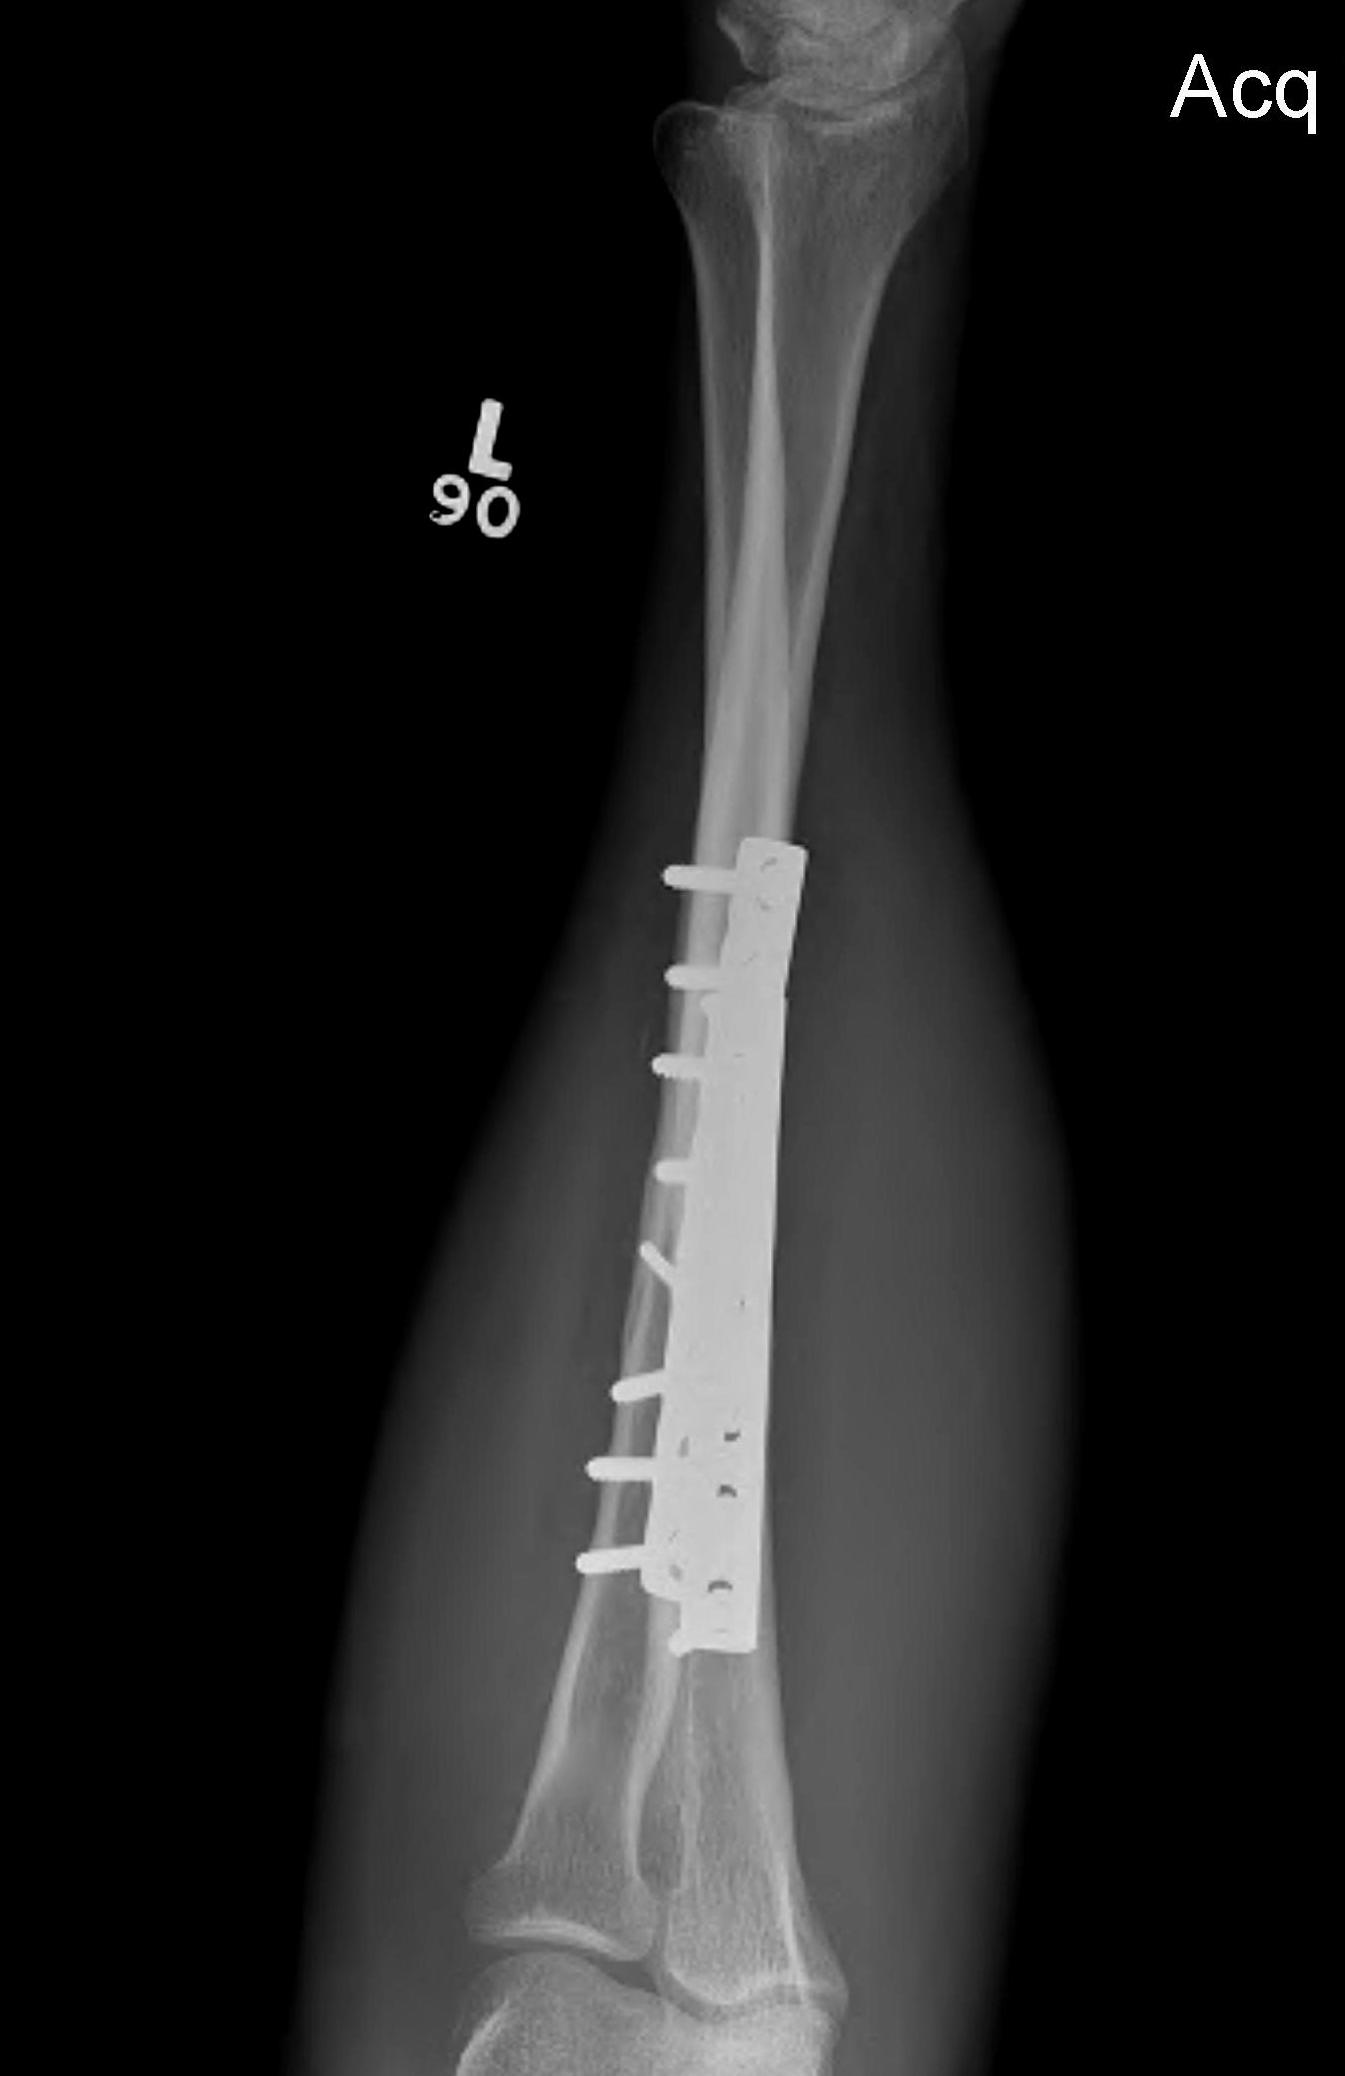

Radial fracture malunion requiring corrective osteotomy

ORIF with DCP plates

Fixation with DCP plates

Revision compression plating + drill intra-medullary canals + autograft